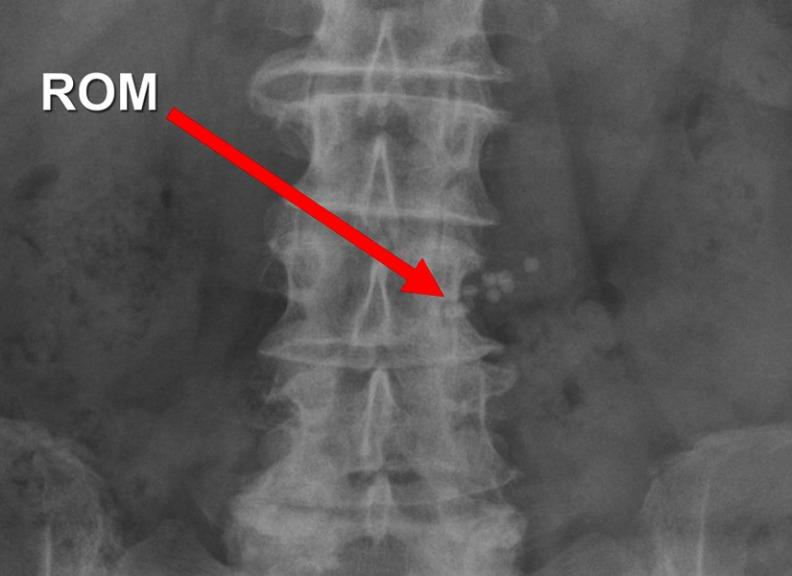

比较不透射线标志物与¹³C标记呼气试验在糖尿病胃轻瘫诊断中的应用

Comparing radiopaque markers and C-labelled breath test in diabetic gastroparesis diagnostics.

Determining gastric emptying is mandatory in the diagnosis of diabetic gastroparesis. Several methods of investigation exist, but none has proven reliable, inexpensive and accessible. In this study, we aimed to compare gastric emptying of radiopaque markers (ROM) and carbon-labelled gastric emptying breath tests for solids (GEBT). We also aimed to determine any association between gastric emptying and patient-reported symptoms, glycemic control and the patients' age, diabetes duration and occurrence of other late complications. Forty-five patients (30 women, 15 men) with diabetes mellitus types 1 or 2 (40, 5) and symptoms of gastroparesis were examined with ROM and GEBT. All were interviewed, filled out symptom questionnaires and had HbA1c levels measured. Forty percent of patients had delayed gastric emptying of ROM, while 55% had delayed gastric emptying of GEBT. Correlation between ROM and GEBT was not significant. Compared to GEBT, sensitivity for a positive ROM test was 0.52, while specificity was 0.74. In women, we found a higher specificity of 0.92, sensitivity 0.47. Difference in HbA1c between patients with positive and negative results was of borderline significance for both tests. GEBT (=0.41, =0.008) correlated with HbA1c. Patients with any late complications of diabetes had higher gastric retention of ROM (=0.028), while patients with polyneuropathy (=0.014) and diabetic wounds (=0.004) had slower emptying with GEBT. None of the methods identified significant associations between gastric emptying and symptom scores, age or diabetes duration. As a measure of gastric emptying, the ROM test has benefits of being affordable and available. Compared to GEBT, the method has low diagnostic reliability. Before continued use, we recommend additional studies validating the test in diabetes patients.

摘要